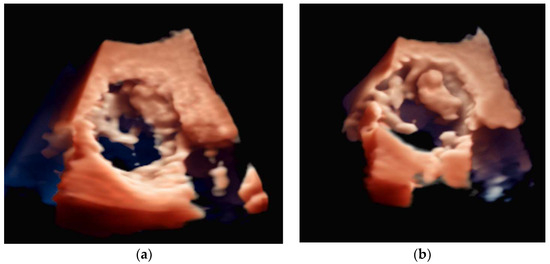

4.2.3. Mitral Valve Repair

4.2.4. Atrial Septal Defect Occlusion